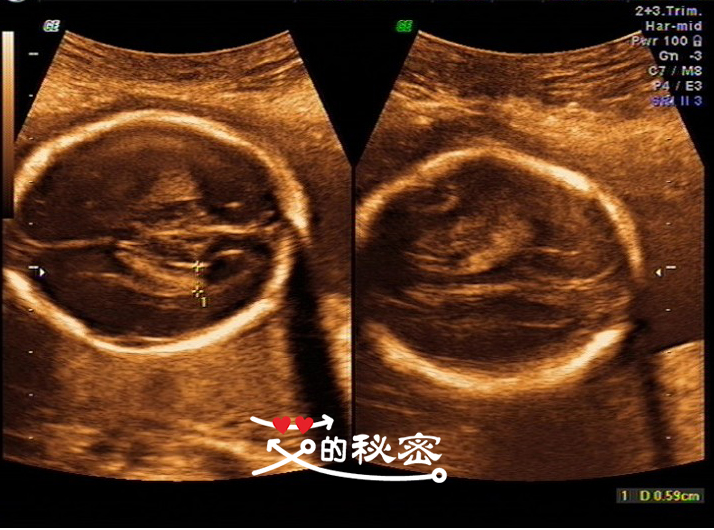

1、胎位:臀位。胎动:可见。胎儿生长指标:BPD55MM,HC202MM,AC183MM,FL41MM。

BPD是指胎儿头两边直径测量的数据,是推算胎儿大小的指标之一。

HC是指头图,AC是指腹围,FL是指股骨长,也就是胎儿大腿骨长度。(HL肱骨长)

5、胎儿头部:颅骨环未见明显缺损,大脑回声可见,脑中线居中,两侧丘脑可见,侧脑室未见增宽,小脑形态未见异常,小脑蚓部可见,后颅窝未见增大。英文的意思:CEREB小脑横径。